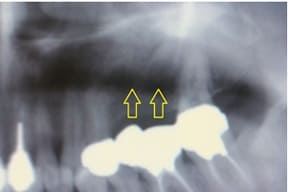

CASE03 臼歯部インプラント ~ブリッジがグラつき始めている~

ブリッジの部分の下顎の骨が吸収をおこし、ブリッジで支えている歯がぐらつき始めている状態。予後を考えた結果、ブリッジで支えることが困難という診断のもと、インプラント治療を施したケースです。